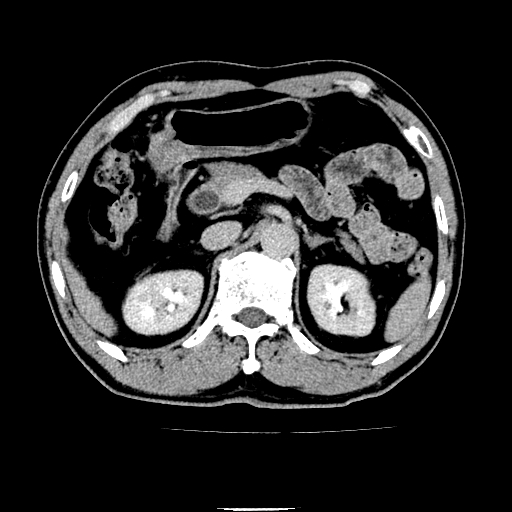

以下是引用chenqiong在2010-3-25 20:56:00的发言:[br]1、胆囊炎,胆囊息肉[br]2、肝内胆管及胆总管扩张,胆总管下端结石[br]3、十二指肠乳头旁憩室

以下是引用zxl51642在2010-3-26 10:47:00的发言:[br]胆囊炎,胆囊息肉,胆总管扩张,但未看到明显肿块,肝内胆管扩张不像恶性,炎性狭窄或阴性结石可能吧,建议mrcp,右肾小囊肿